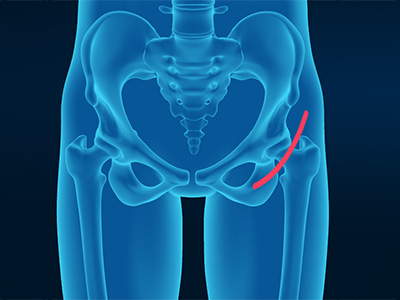

Direct Anterior Hip Replacement Direct Superior Hip Replacement

Direct Superior Hip Replacement Bikini Incision Hip Replacement

Bikini Incision Hip Replacement Hip Reconstruction